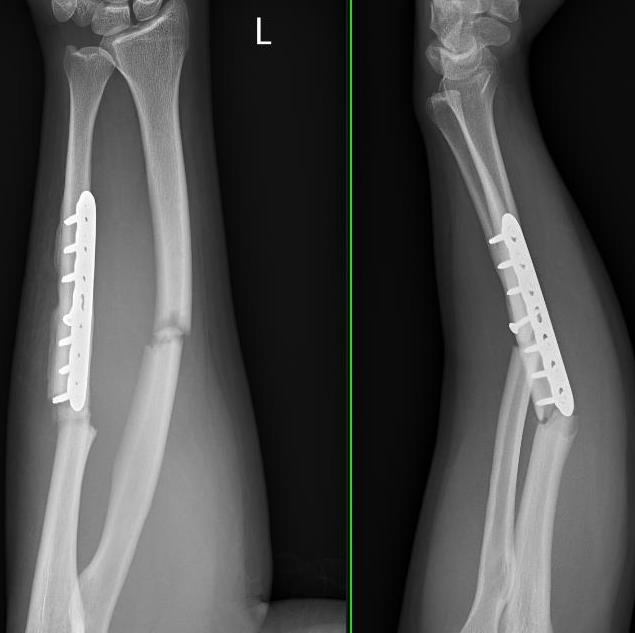

Revision compression plating + drill intra-medullary canals + autograft

Results

- 35 forearm nonunions treated with revision compression plating and bone grafting

- average defect 2 cm

- 100% union